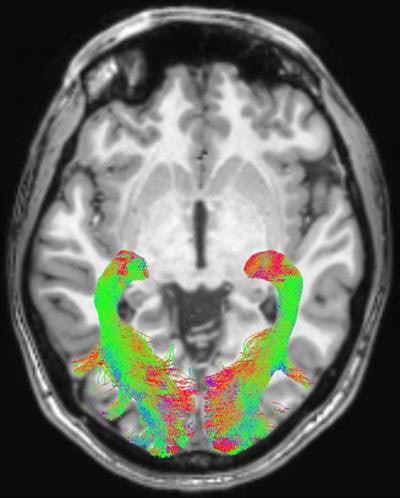

Left and right optic radiation image is overlaid onto a T1-weighted axial volume image. Optic radiation images were obtained based on diffusion-weighted volume images through constrained spherical deconvolution fitting and related tractography. Each bundle was automatically colored according to tract main directionality: red for left to right, green for anterior to posterior, and blue for inferior to superior. Image courtesy of the RSNA."This protocol could be used for longitudinal studies to help understand the progression of visual alterations in the course of the disease and to assess positive or negative effects of pharmacologic treatments on visual structures," the authors wrote.

The group found statistically significant abnormalities within the visual system brain structures of patients with Parkinson's disease, compared with the healthy control subjects. These included changes in optic radiations, reduced white-matter concentration, and reduced optic chiasm volume.